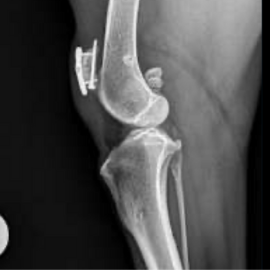

Resolución de fractura de rótula mediante tornillo de compresión y placa bloqueada. A propósito de un caso clínico.